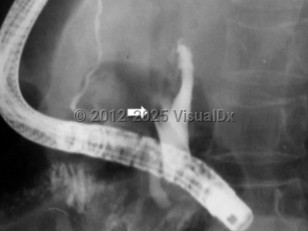

Ascariasis

Ascaris lumbricoides is an intestinal parasite of humans and is the most common human helminthic infection worldwide, estimated to affect more than a billion people. Larvae and adult worms live in the small intestine of humans, and worm eggs are then passed in feces. Infection occurs when infective eggs are ingested, either from putting hands or fingers with contaminated dirt in the mouth or by eating contaminated fruits or vegetables that have not been sufficiently washed, peeled, or cooked. Outdoor defecation or the use of human feces as fertilizer can contaminate the soil with eggs. Eggs can remain viable through extreme temperatures and for several months in sewage.